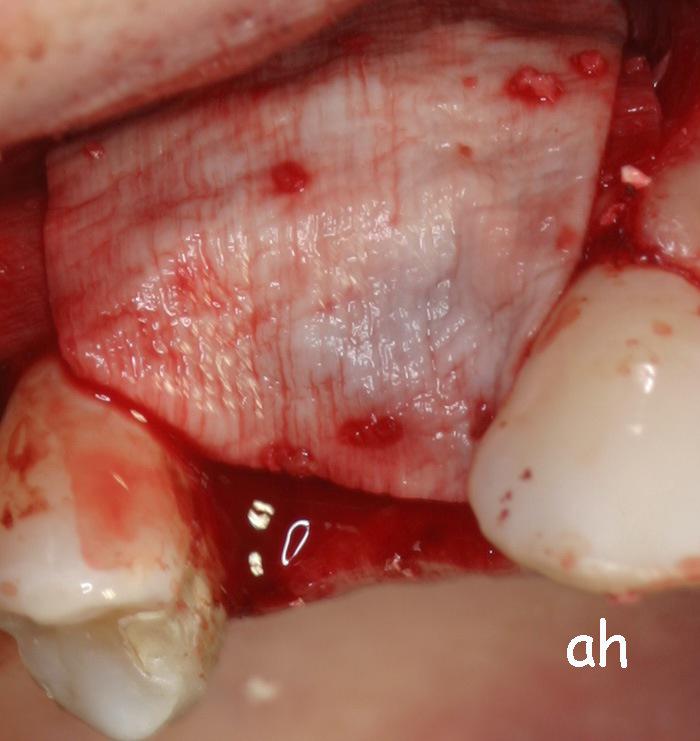

Exemple 11: Pendant l'implantation on remarque un manque d'os sur la partie externe, les spires de l'implant sont visibles.

Exemple 11: Une greffe d'os est effectuée afin de compenser l'épaisseur d'os manquante.

Exemple 11: Le tout est recouvert d'une membrane collagène.

Exemple 11: Après cicatrisation environ 6 mois, le moignon est vissé sur l'implant.

Exemple 11: La couronne céramique en place.